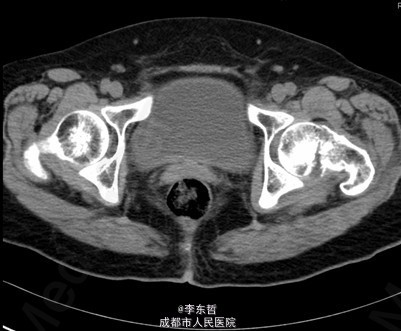

患者女,61岁,因“摔伤致左髋疼痛伴活动受限4+天”入院。患者自诉4+天前在浴室里不慎滑倒,左髋部着地,当时感左髋部剧痛,伴有活动受限,不伴有恶心呕吐、头痛头昏等不适。患者随即被家属送至当地医院,完善X线片后提示左股骨颈骨折,给予对症支持治疗后,患者家属为求进一步诊治,转至我院急诊科,以左股骨颈骨折送入我科。

查体:T:37.2oC,P:96次/分,R:22次/分,BP:113/62mmHg。神志清楚,无病容,皮肤巩膜无黄染,全身浅表淋巴结未见肿大。颈静脉正常。心界正常,心律齐,各瓣膜区未闻及杂音。胸廓未见异常,双肺叩诊呈清音,双肺呼吸音清,未闻及干湿啰音及胸膜摩擦音。腹部外形正常,全腹柔软,无压痛及反跳痛,腹部未触及包块,肝脏肋下未触及,脾脏肋下未触及,双肾未触及。双下肢无水肿。专科查体:视:双下肢不等长,左下肢外旋畸形,左髋肿胀,周围皮肤未见红肿,溃疡,窦道,瘘管等形成;触:双下肢皮肤感觉正常,末梢循环良好,足背动脉可扪及,左髋肿胀,触压痛明显,股骨颈叩击痛阳性,未闻及骨摩擦音及摩擦感;动量:双下肢肌力及肌张力正常,右髋、双膝、踝关节活动度良好,左下肢较右侧缩短约2cm,左髋因疼痛拒动。 辅助检查X片示:左股骨颈骨折,远断端向上方错位,左髋关节在位。骨盆骨质疏松。